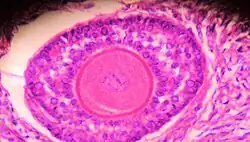

.jpg) Histology section of a mature ovarian follicle. The oocyte is the large, round, pink-staining cell at top center of the image. | |

Ovarian follicles are the basic units of female reproductive biology. Each of them contains a single oocyte (immature ovum or egg cell). These structures are periodically initiated to grow and develop, culminating in ovulation of usually a single competent oocyte in humans.[5] They also consist of granulosa cells and theca of follicle.

Once a month, one of the ovaries releases a mature egg (ovum), known as an oocyte. The nucleus of such an oocyte is called a germinal vesicle[6] (see picture).

Granulosa cells or follicular cells are cells that surround the oocyte within the follicle; their numbers increase directly in response to heightened levels of circulating gonadotropins or decrease in response to testosterone. They also produce peptides involved in ovarian hormone synthesis regulation. Follicle-stimulating hormone (FSH) induces granulosa cells to express luteinizing hormone (LH) receptors on their surfaces; when circulating LH binds to these receptors, proliferation stops.[7]

The granulosa cells, in turn, are enclosed in a thin layer of extracellular matrix – the follicular basement membrane or basal lamina (fibro-vascular coat in picture). Outside the basal lamina, the layers theca interna and theca externa are found.